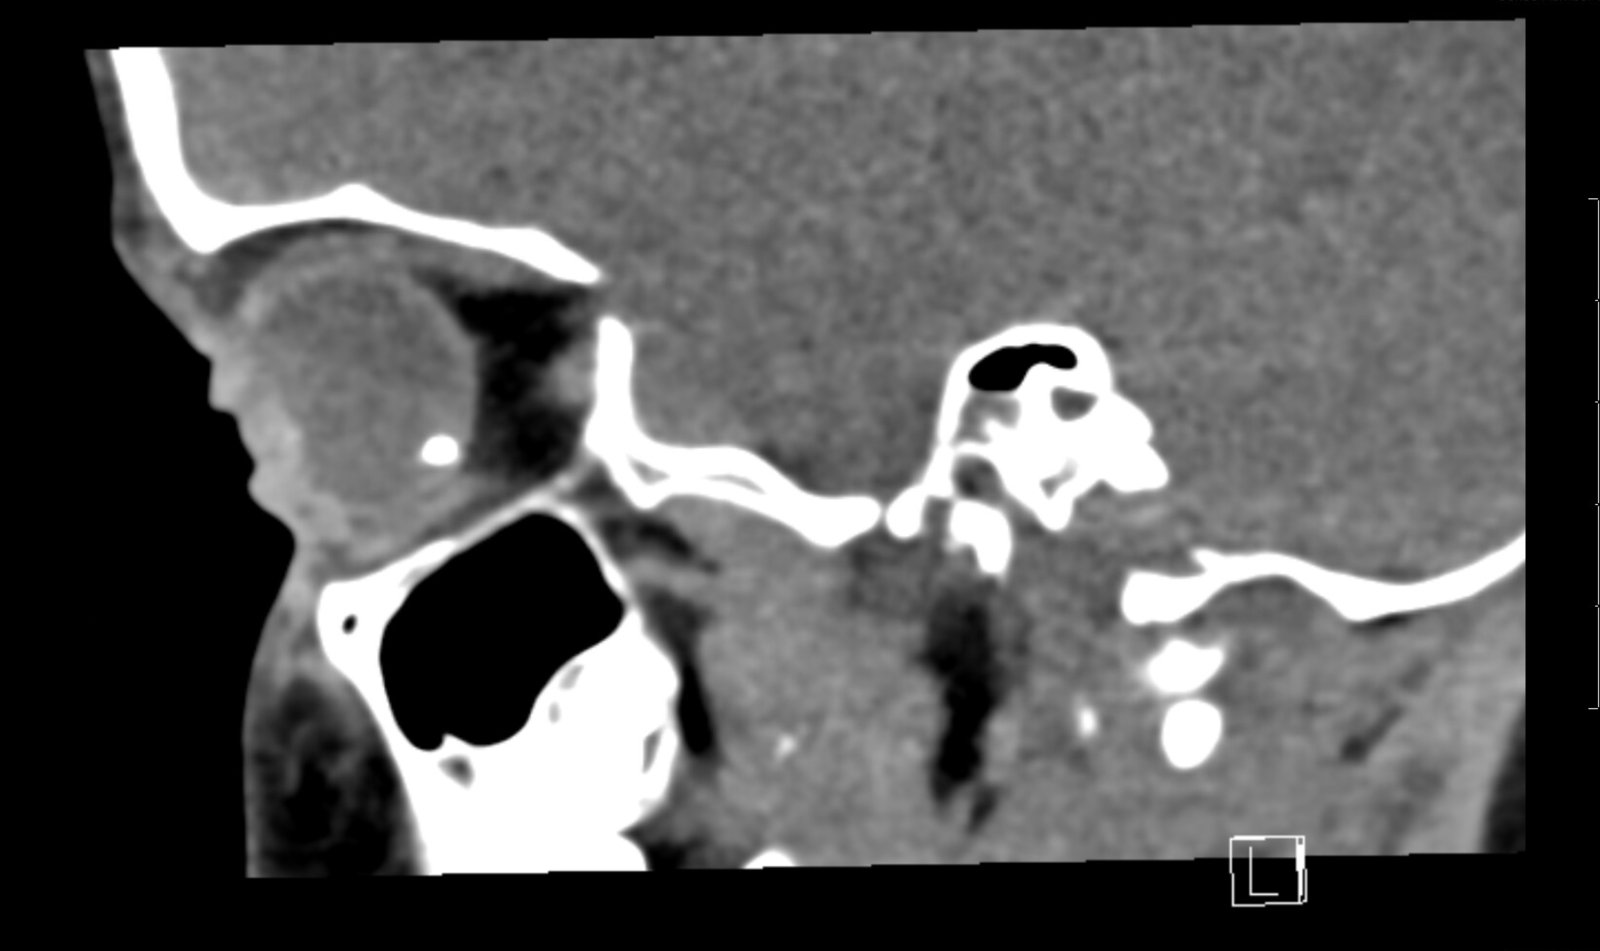

Computed tomography (CT) of the orbits was performed without contrast. There was a spherical high-density foreign body in the right posterior globe, inferiorly, at the 5 o’clock position measuring 3mm in diameter. No hematoma, lens dislocation, or significant decrease in volume was noted.